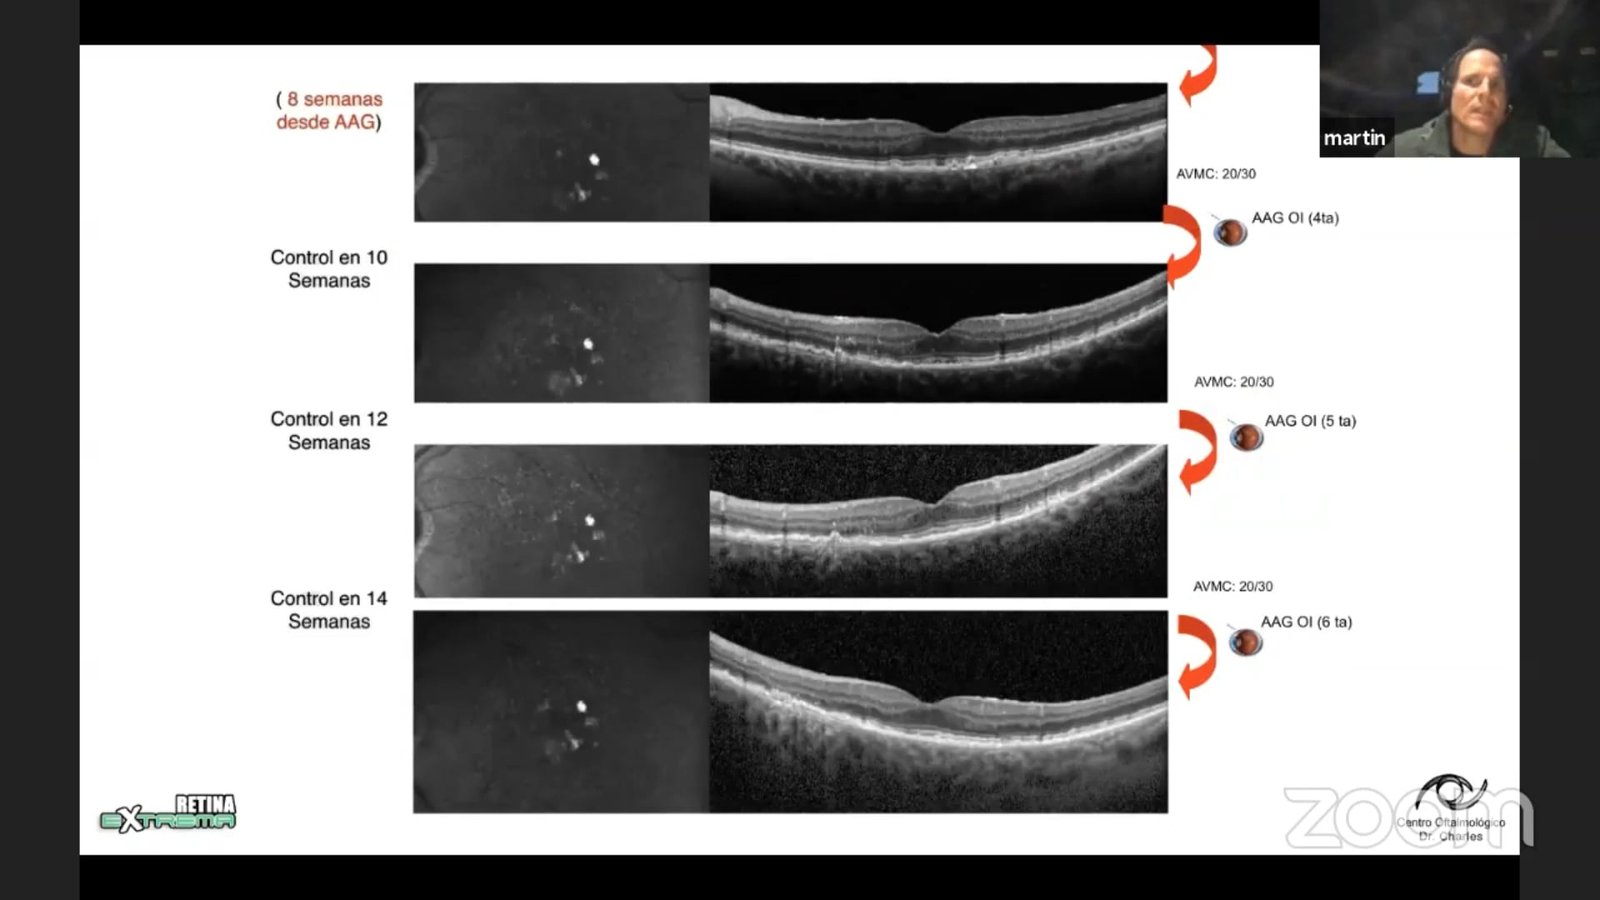

Treat and Extend